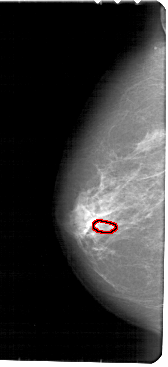

A_1840_1.LEFT_MLO

FILE: A_1840_1.LEFT_MLO.OVERLAY

TOTAL_ABNORMALITIES 1

ABNORMALITY 1

LESION_TYPE CALCIFICATION TYPE PLEOMORPHIC DISTRIBUTION CLUSTERED

ASSESSMENT 4

SUBTLETY 2

PATHOLOGY BENIGN

TOTAL_OUTLINES 1

BOUNDARY